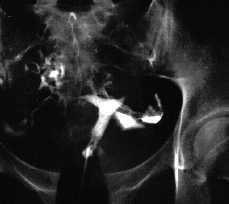

En histerosalpingografía practicada con posterioridad se objetiva un útero de morfología normal, así como ambas trompas permeables, compatible con la normalidad. No se dibujan trayectos fistulosos.

-- Descartamos la existencia de fístula uteroperitoneal mediante la práctica de una HSG.

Figura 5. Imágenes de la histerosalpingografía de control practicada 4 meses más tarde.